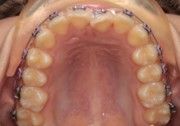

The IOS Mini Cinch Back Plier demonstrated superior control and a significantly reduced risk of bracket debonding and wire deformation compared to the regular Hammerhead plier from a different brand. Wire bends achieved with the IOS Mini Cinch Back Plier maintained integrity even under high-torque activation. The following images illustrate key differences in bend quality, wire distortion, and proximity to the bracket between the IOS Mini Cinch Back Plier and the conventional Hammerhead plier.